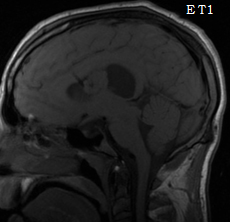

Une tumeur mise à sec

Cas Clinique

Dr Arnault Tauziède-Espariat AP-HP Lariboisière - Paris

Données cliniques :

Patient âgé de 22 ans, sans antécédents, adressé en urgence pour une crise comitiale tonico-clonique généralisée cédant après injection de Valium.

Scanner cérébral : lésion intra-ventriculaire du ventricule latéral gauche, prenant le contraste. Hospitalisation et bilan.

Quel est votre diagnostic ?